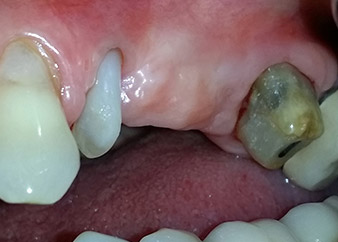

Two-months interim result

Figures 17 and 18 show the clinical result two months after the surgery. Tooth 24 exhibited reduced mobility of Miller class 1, and the soft tissues were free of inflammation. Probing was avoided at this point of time to prevent reinfection and to avoid violating the epithelial attachment. A control visit was scheduled for reentry and placement of healing abutments, six months after the insertion of the implants.

Two months after the surgery, the patient was pain-free.

Fig. 17: Two months after the surgery, the patient was pain-free and the area was free of inflammation.

after the surgery

Fig. 18: Tooth 24 now showed less mobility.

Prognosis and restorative options

At the two-months recall, the mobility of the remaining “dental element” 24 was already reduced from Miller 2 to Miller 1. The soft tissue attachment was on the level of the neighbouring tooth 23. Moreover, there were no endodontic or periodontal symptoms, so its prognosis may have to be readjusted.

However, as most of the buccal and proximal bone is missing and the composite build-up extends to the apical section of the root, a higher reattachment level is not to be expected due to biologic reasons (Sculean et al., 2008).